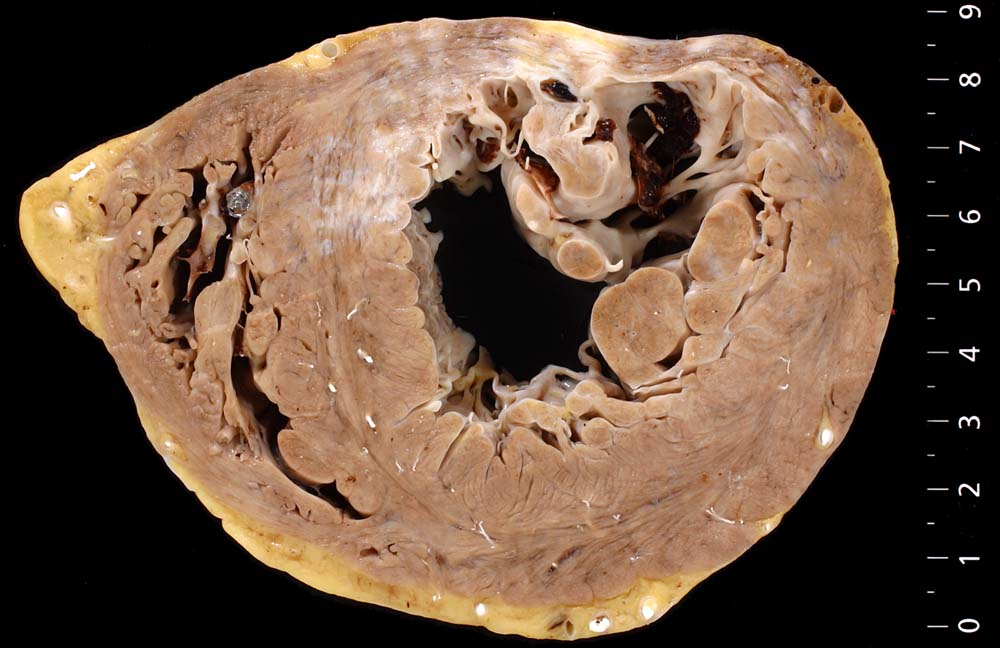

Eine restitutio ad integrum nach abgelaufener Myokardnekrose ist nicht möglich. Wird das Ischämieereignis überlebt, kommt es zu einer reparativen Regeneration mit Ersatz der Muskulatur durch kollagenreiches Narbengewebe. Dieser Vorgang setzt etwa ab dem 9. Tag nach Infarkt ein und dauert bis zur vollständigen narbigen Ausheilung bei transmuralem Infarkt etwa 50 Tage. Makroskopisch imponiert die Narbe als fasriges weisses derbes Areal. Von einem Infarkt spricht man, wenn die Nekroseareale einen Durchmesser von mindestens 3cm Durchmesser haben. Ab dieser Grösse kann klinisch das Bild eines Myokardinfarktes ausgelöst werden. Kleinere, makroskopisch sichtbare Narben werden als grobfleckige Myokardfibrose (> 873) (> 234) bezeichnet.

Komplikationen:

Im Bereich grösserer Narben ist das Myokard verdünnt. Bei 8% der transmuralen Infarkte entsteht im Bereich der Narbe ein Herzwandaneurysma (> 2088) mit oder ohne wandständige Thrombose (> 348). In 5-15% führen die Thromben zu systemischen Embolien. Von der Randzone der Aneurysmen gehen oft hartnäckige ventrikuläre Rhythmusstörungen aus. Grosse Narben führen zu einer Verminderung der Pumpleistung mit Herzinsuffizienz.